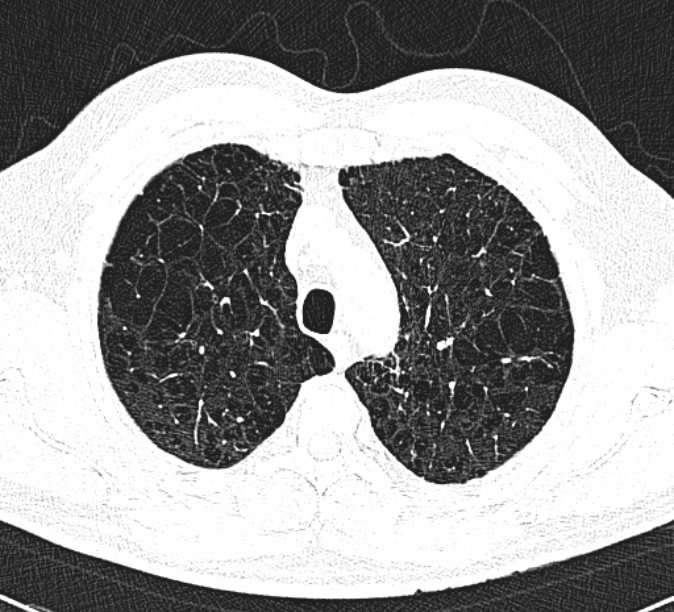

Doctors usually confirm COPD with:

Early diagnosis is crucial. Many people only get diagnosed when their lung function is already severely reduced.